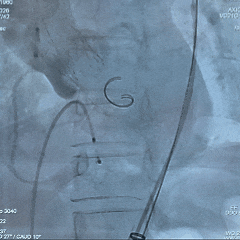

术中影像

根部造影

瓣叶钙化明显,瓣叶活动差,中度反流

直头导丝顺利跨瓣

猪尾导管测量跨瓣压差约60mmHg

20mm球囊预扩

小弯侧微腰,少量漏,左冠显影,右冠无显影

瓣膜0位初始定位释放

全展开位造影评估

瓣下约 3mm,左右冠均显影,少量反流

瓣膜稳定脱钩

无位移,无弹跳,无张力释放

根部造影评估

位置可,形态受限,可见中重度反流,左右冠均显影

20mm球囊后扩

可见瓣架底端扩开,瓣膜形态改善

最终造影可见瓣周漏,符合术前预判

超声可见左无对合缘轻度反流,整体瓣架形态较圆,左无钙化处呈“D”型,测量峰值流速为1.6m/s